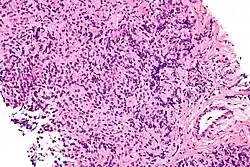

Large-cell lymphoma

| Micrograph of a primary mediastinal large B-cell lymphoma, a type of large-cell lymphoma. H&E stain. | |